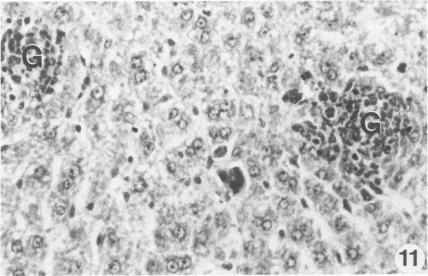

The pathogenesis of experimentally induced cecal amebiasis in gerbils (Meriones unguiculatus) was studied from 5 to 60 days after inoculation. Ulcerative lesions were noted 10 to 60 days after inoculation. The sequential development of lesions was asynchronous and progressed from destruction of the interglandular epithelium and of glandular crypt elements to loss of mucosa and formation of granulomatous lesions in the submucosa involving the muscularis mucosae. Pathologic changes in the liver correlated with the formation of ulcerative cecal lesions. Subacute hepatic changes showed lymphocytic portal infiltrate, Kupffer cell hyperplasia, multinucleated giant cells, granuloma formation, and sinusoidal mononuclear and granulocytic infiltrates. Metastatic amebic liver abscesses occurred as early as 10 days after inoculation, and small abscesses were found in the portal areas of the right liver lobe. The sequential development and pathologic manifestation of the infection and the usefulness of the gerbil for the study of human intestinal amebiasis are discussed.

在接种后5至60天,对沙土鼠(长爪沙鼠)实验性诱导盲肠阿米巴病的发病机制进行了研究。接种后10至60天观察到溃疡性病变。病变的连续发展是异步的,从腺间上皮和腺隐窝成分的破坏发展到黏膜丧失,并在涉及黏膜肌层的黏膜下层形成肉芽肿性病变。肝脏的病理变化与盲肠溃疡性病变的形成相关。亚急性肝脏变化表现为淋巴细胞门静脉浸润、库普弗细胞增生、多核巨细胞、肉芽肿形成以及窦状隙单核细胞和粒细胞浸润。转移性阿米巴肝脓肿最早在接种后10天出现,在右肝叶门静脉区域发现小脓肿。讨论了感染的连续发展和病理表现以及沙土鼠在人类肠道阿米巴病研究中的用途。